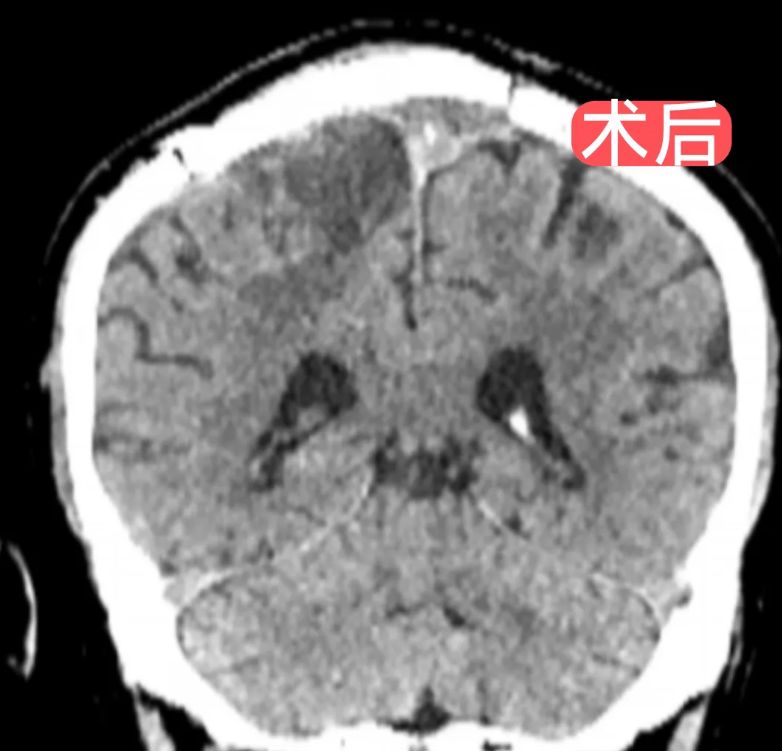

手术过程中,在欧海荣主任医师的指导下,由李越主任医师领衔主刀,李辉副主任医师、陈思医师默契配合。团队在显微镜下以"抽丝剥茧"般的精细操作,完整剥离肿瘤,并成功修补重建受侵犯的矢状窦,全程完好保护周围脑组织与重要血管。

术后8小时,患者如期清醒。经过医护团队的精心治疗和护理,患者恢复良好,已顺利康复出院。